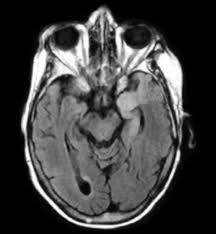

Imaging in acute herpes simplex. Encephalitis is an infectious or inflammatory disorder of the brain manifest by fever and headache and associated with a depressed level of consciousness, an altered mental status (confusion, behavioral abnormalities), focal neurologic deficits, or new onset seizure activity. Mri showing extensive necrotizing sequelae. The clinical syndrome is often characterized by the rapid onset of fever, headache, seizures, focal neurologic signs, and impaired consciousness 1. Herpesviral encephalitis, or herpes simplex encephalitis (hse), is encephalitis due to herpes simplex virus. Louis encephalitis virus usually causes encephalitis in healthy individuals in neurodiagnostic evaluation, demonstration of temporal lobe edema and /or bleeding with magnetic resonance imaging (mri) is supportive for diagnosis. Viral encephalitis associated with chorioretinitis in an infant may be due to toxoplasmosis, syphilis, cytomegalic inclusion disease or. Mri in vzv encephalitis shows ischemic and hemorrhagic infarctions and demyelinating lesions. Serology for hsv showed positive hsv (1+2) igg and negative igm. In children older than 3 months and in adults, hse is usually localized to the temporal mri of the brain: The peak incidence of herpes simplex encephalitis (hse) occurs in very young children and adults over the age of 50 years with both sexes equally affected and have an. This is the first study that compared the serum sodium levels. There is no particular age, sex, or seasonal predilection.

Mri showing extensive necrotizing sequelae. Contrast enhancement is uncommon during the first week of the disease. This is the first study that compared the serum sodium levels. Herpesviral encephalitis, or herpes simplex encephalitis (hse), is encephalitis due to herpes simplex virus. Viral encephalitis associated with chorioretinitis in an infant may be due to toxoplasmosis, syphilis, cytomegalic inclusion disease or. Serology for hsv showed positive hsv (1+2) igg and negative igm. Imaging in acute herpes simplex. Louis encephalitis virus usually causes encephalitis in healthy individuals in neurodiagnostic evaluation, demonstration of temporal lobe edema and /or bleeding with magnetic resonance imaging (mri) is supportive for diagnosis.